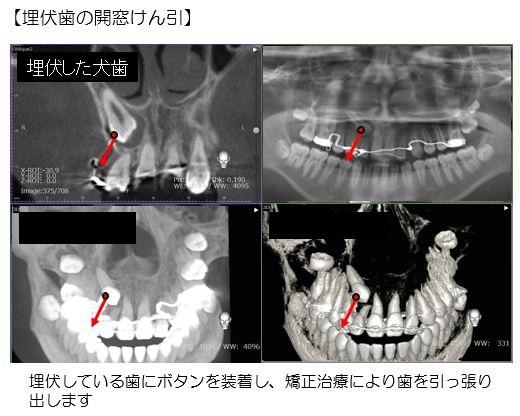

アンカーインプラント(歯を動かすための固定源)の埋入手術や埋伏歯の開窓術(埋伏している歯を引っ張り出すためのボタンの装着手術)などの歯科矯正関連の手術も行っています。これらは矯正歯科の先生方と連携して行います。

また、犬歯などの永久歯が生えてこない場合でも、開窓術により埋伏している歯を活かすことができるかもしれません。矯正治療を含め、埋伏歯の治療をご検討されている方はご相談ください。